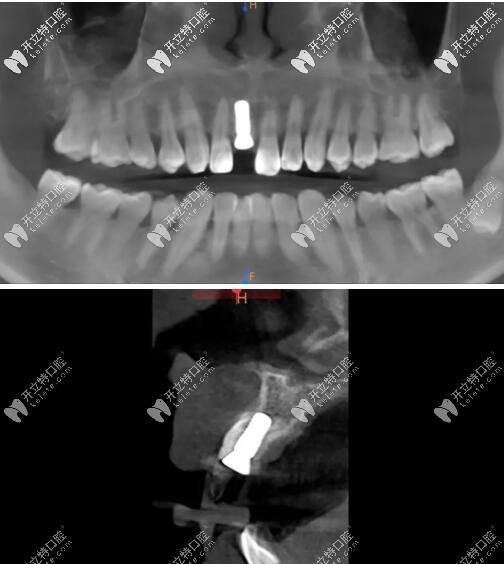

術(shù)后CBCT顯示植入正確的三維位置,種植體唇側(cè)骨量充足;

瑞士iti鈦親水BL 4.1mm*10mm種植體